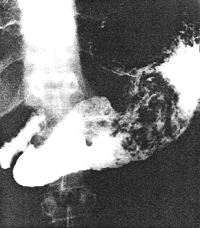

Case 37.1. D.R., 40 year old male had a long history of ethanol abuse and insulin- dependent diabetes mellitus which had been treated inadequately. For several weeks there had been dyspepsia, loss of appetite and nausea. Radiologically primary and secondary oesophageal peristaltic waves were normal. After an overnight fast the stomach contained food residues; the pyloric aperture was patent, measuring 9.0. mm in diameter (Fig. 37.1A). Gastric peristaltic waves were decreased both in frequency (i.e. less than 3 per minute) and intensity (i.e. failing to "bi-sect" the organ). The pyloric sphincteric cylinder was in a state of partial contraction most of the time (Fig. 37.1B). Cyclical contraction and relaxation of the cylinder, normally occurring at a frequency of 3 per minute (Chaps. 13, 15), was lacking. No obstructing lesion was seen at the pylorus and the duodenum appeared normal. Sonographically the gall bladder, liver, spleen and kidneys were normal; there was no ascites. The patient refused endoscopic examination.

A![]() |

B![]() |

| Fig. 37.1. A,B. Case D.R. A Food residues in stomach. Pyloric aperture patent. Gastric peristaltic activity diminished. B Pyloric sphincteric cylinder (arrows) contracted most of the time. |